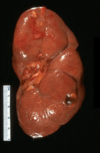

How does a Renal Cell tumor present grossly?

• Hemorrhage and Necrosis are common - hemorrhage most likely related to highly vascularized tissue arising from VHF mutations leading to HIF-1alpha and ultimately VEGF release

What type of cancer is seen here?

• KEY Features?

• what would you expect to see on microscopic examination?

Renal Clear Cell Carcinoma

• Key Features

• solitary, well defined, polar

• YELLOW, cysts , necrosis, HEMORRHAGE

MICROSCOPIC FEATURES:

• Clear LIPID FILLED cells with CHICKEN WIRE vessel formation found between the cells